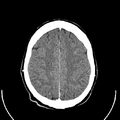

معرض الصور